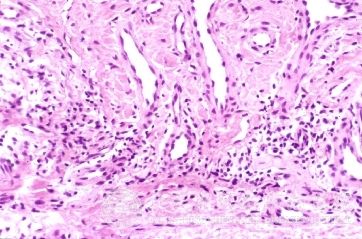

自敏性皮炎的发病机制是什么?自敏性皮炎是一种比较多发、常见、病情比较复杂的皮肤病,自敏性皮炎的出现常给人们的肌肤造成各种皮肤损害,因此一定要及时的采取自敏性皮炎治理措施。临床上治疗自敏性皮炎的方法多种多样,及时治疗关键是了解自敏性皮炎的发病机制,那么自敏性皮炎的发病机制是什么呢?

北京京城皮肤医院指出,自敏性皮炎的发病机制:自敏性皮炎患者原有皮肤病,多数为湿疹病灶,经外用药或不适当的处理后,局部炎症加剧,出现渗出或细菌感染,然后患者对其自身皮肤组织所产生的蛋白质或自体组织蛋白质,合并脓性渗液中的细菌毒素和组织的化学物质发生过敏所致。